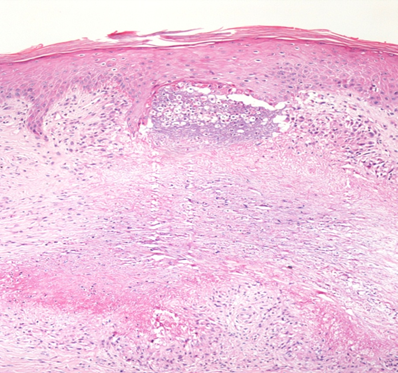

With the diagnostic hypotheses of rheumatoid nodule, granuloma annulare, erythema elevatum diutinum and sarcoidosis, incisional biopsy was performed and histopathological examination showed palisaded epithelioid granulomas in the superficial and deep dermis, without plasma cells, with central fibrinoid necrosis, in addition to vascular ectasia with tumefied endotheliocytes and fibrin thrombi. The process touched the epidermis in foci, suggesting areas of transepidermal elimination (Figures 4 & 5).

Figure 4 H&E, 40x: presence of palisade granulomas with central necrobiosis.

Figure 5 The lesion approaches the epidermis, outlining transepidermal shedding of necrobiotic collagen.